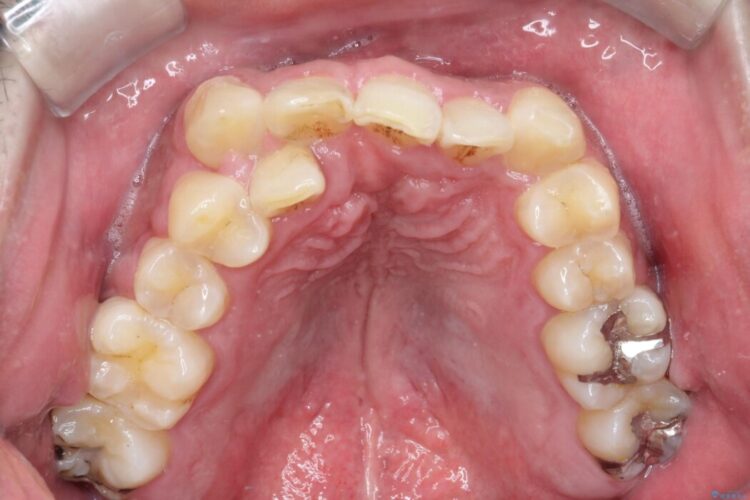

反対になっている嚙み合わせを改善したいとご来院されました。

診査の結果、上下左右4番の歯を抜歯し、審美装置にて反対咬合と叢生を改善していくこととしました。

骨格性Ⅲ級を示しましたが、構成咬合位がとれたことから反対咬合と叢生改善のため、上下左右第一小臼歯を抜歯しワイヤー矯正を行いました。途中、バイトアップを行っています。